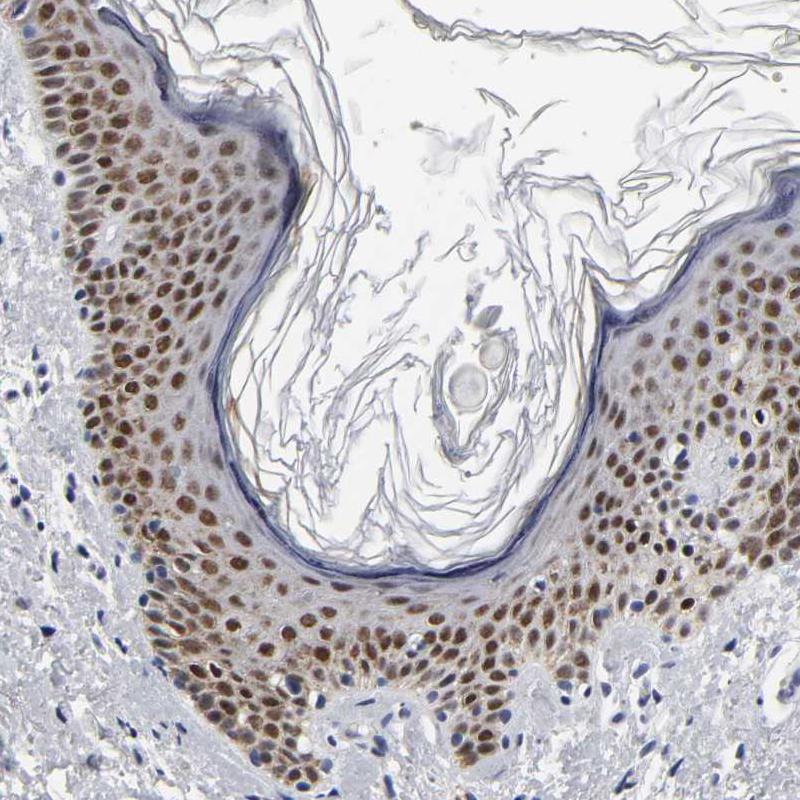

Immunohistochemical staining of human prostate shows strong nuclear positivity in glandular cells.